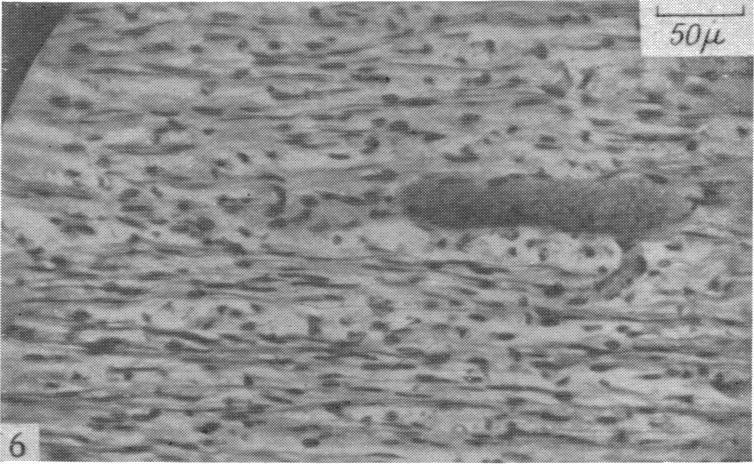

The degeneration and re-innervation of grafted nerves.

J Anat. 1942 Jan;76(Pt 2):143-166.7.